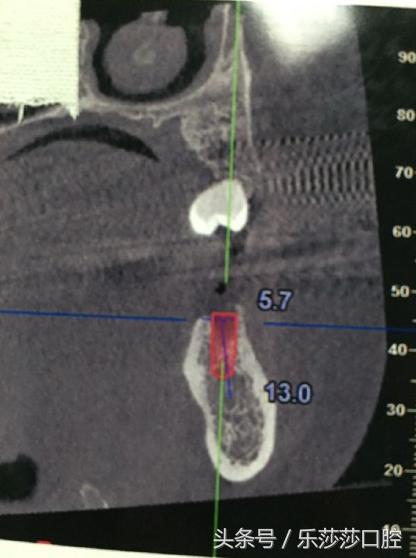

进行口腔检查,拍一个口腔全景片,了解牙齿、牙槽骨的具体情况,如果牙槽骨有吸收的现象,为避免了种植区骨量不足,要进行植骨。

这就是要种牙的位置哦~